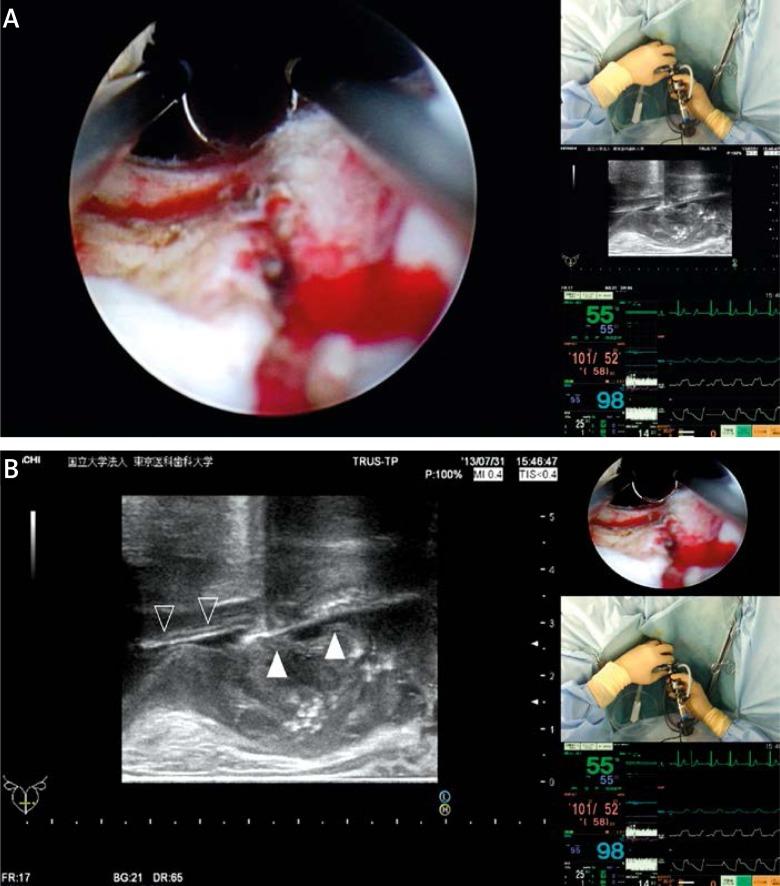

The head-mounted display (HMD) is a new image monitoring system. We developed the Personal Integrated-image Monitoring System (PIM System) using the HMD (HMZ-T2, Sony Corporation, Tokyo, Japan) in combination with video splitters and multiplexers as a surgical guide system for transurethral resection of the prostate (TURP). The imaging information obtained from the cystoscope, the transurethral ultrasonography (TRUS), the video camera attached to the HMD, and the patient's vital signs monitor were split and integrated by the PIM System and a composite image was displayed by the HMD using a four-split screen technique. Wearing the HMD, the lead surgeon and the assistant could simultaneously and continuously monitor the same information displayed by the HMD in an ergonomically efficient posture. Each participant could independently rearrange the images comprising the composite image depending on the engaging step. Two benign prostatic hyperplasia (BPH) patients underwent TURP performed by surgeons guided with this system. In both cases, the TURP procedure was successfully performed, and their postoperative clinical courses had no remarkable unfavorable events. During the procedure, none of the participants experienced any HMD-wear related adverse effects or reported any discomfort.

头戴式显示器(HMD)是一种新型图像监测系统。我们使用HMD(HMZ-T2,索尼公司,东京,日本),结合视频分配器和多路复用器,开发了个人集成图像监测系统(PIM系统),作为经尿道前列腺切除术(TURP)的手术引导系统。从膀胱镜、经尿道超声检查(TRUS)、连接到HMD的摄像机以及患者生命体征监测仪获取的成像信息,由PIM系统进行分割和整合,并使用四分屏技术通过HMD显示合成图像。主刀医生和助手佩戴HMD,可以以符合人体工程学的高效姿势同时连续监测HMD显示的相同信息。每个参与者可以根据操作步骤独立重新排列合成图像中的各个图像。两名良性前列腺增生(BPH)患者在该系统引导下由外科医生进行了TURP手术。在这两个病例中,TURP手术均成功完成,术后临床过程未出现明显不良事件。在手术过程中,没有参与者经历任何与佩戴HMD相关的不良反应,也没有人报告有任何不适。